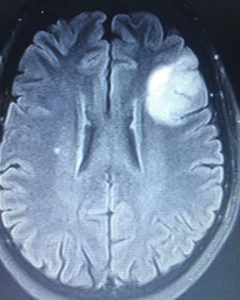

Local anesthesia is one of the oldest forms of anesthesia and is adequate for opening the skull to remove a tumor. A patient with a tumor in the left frontal or temporal region such as this young lady that I operated upon recently can be monitored for their speech function while the tumor is removed under local anesthesia.